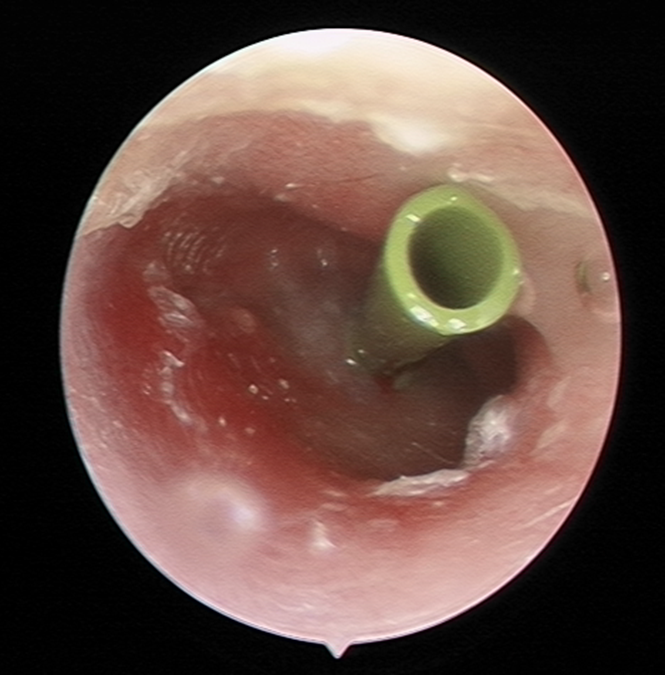

图片

3分泌性中耳炎内镜检查显示鼓膜内陷,橙红油亮。